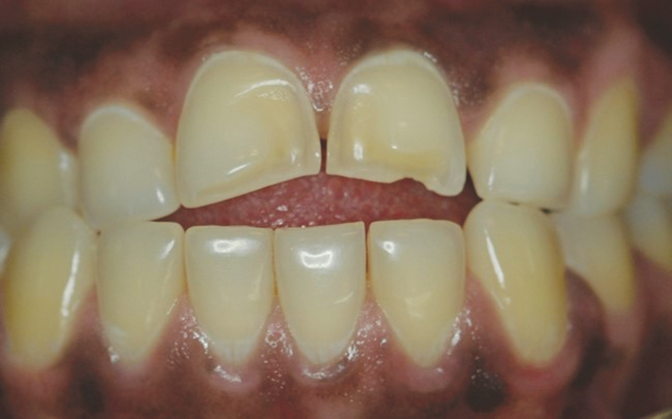

Another intrinsic factor is the patient's gastric acid entering the oral cavity. The source of intrinsic stomach acid may range from rumination or gastroesophageal reflux to chronic alcoholism, pregnancy, or vomiting caused by anorexia nervosa or bulimia nervosa.13 Figure 1 through Figure 3 show the radiographic presentation and clinical examples of dental erosion in advanced stages in the same patient caused by the combination of bulimia nervosa and chronic alcoholism.

Fig 2. Facial erosion of maxillary (Fig 2) and mandibular (Fig 3) anterior teeth.

Figure 2